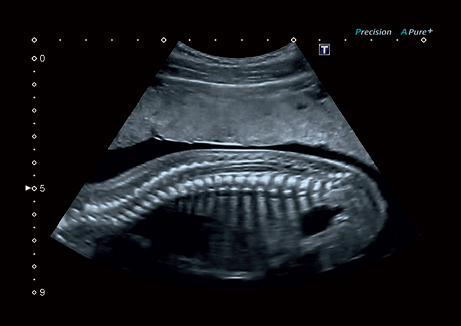

• Precision Imaging - технология получения изображений мелких деталей с четко очерченными границами и высокой однородностью

Precision Imaging:

Да

• Прецизионная визуализация (Precision Imaging) для послойного дифференцирования тканевых структур и высокой детализации;